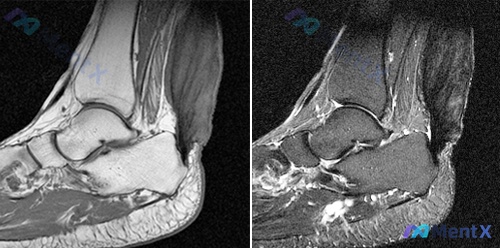

整理了一份踝关节MRI的病例资料,第一眼容易走偏,放出来和大家讨论一下。 影像核心表现(矢状位): - 足底软组织(跟骨下方区域)可见多发结节状/条片状T2高信号聚集 - 对应T1加权像呈混杂信号,部分区域低信号 - 跟腱走行连续,无明显增粗或断裂 - 距骨、跟骨及胫骨远端骨质信号无明显异常,无骨髓...